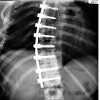

Коррекция сколиоза через торакофренолюмботомию

Коррекция сколиоза торакотомией. Хирургическая техника, в соответствии с которой разрез делается вдоль десятого межреберного пространства, начиная от подмышечной осевой линии и продолжая вперед. Затем рассекают мягкие ткани и открывают грудную клетку, устраняют сдавливание нервных корешков и тканей спинного мозга, иммобилизируют несколько позвонков для стабилизации позвоночника и устраняют болевой синдром. Коррекция сколиоза путем торакофренолимботомии показана при деформации более 40 градусов, прогрессировании заболевания, сильных болях или серьезных косметических дефектах, влияющих на качество жизни и работоспособность пациента.